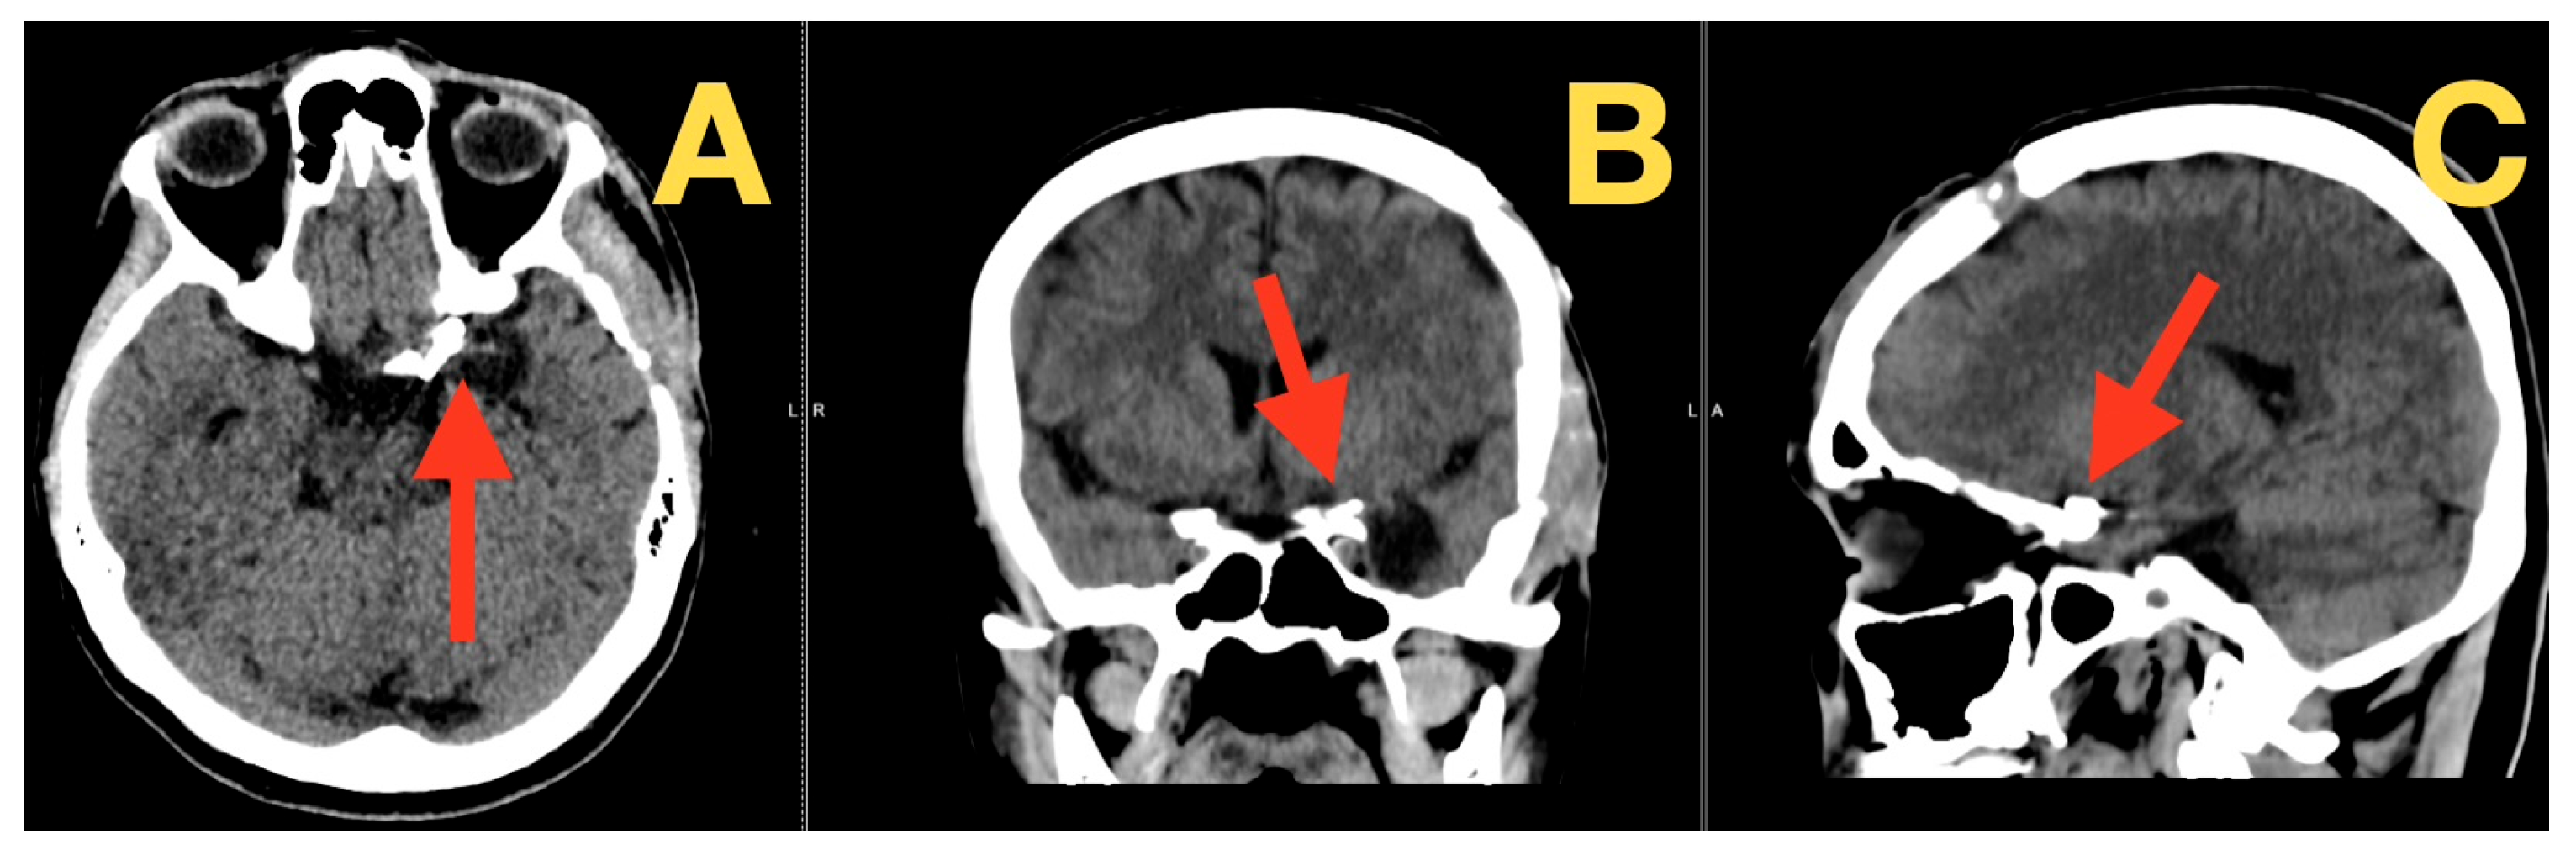

A Ruptured Tri-Lobulated ICA–PCom Aneurysm Presenting with Preserved Neurological Function: Case Report and Clinical–Anatomical Analysis

2. Case Presentation

- Most likely diagnosis: Aneurysmal subarachnoid hemorrhage (SAH); based on the characteristics of the headache, the intensity of pain at onset, the pronounced meningeal signs and photophobia, and the lack of focal neurological deficits (Hunt–Hess 1; WFNS 1; NIHSS 0).